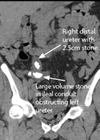

In the sixth article in this series the authors describe endourology nightmares involving ileal conduits and calculi. Case 1 A 69-year-old man who had a cystectomy and ileal conduit for muscle invasive bladder cancer, presented with an acute kidney injury...